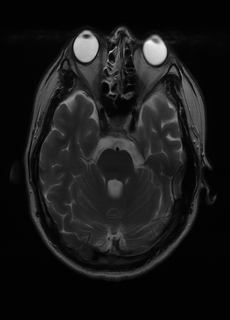

As we observe from the right image in Fig. 2, our BRM, both from MIMO and SISO settings, predicts the performance of dedicated models with a high correlation. We further choose the best three , and perform the last stage of fine-tuning accordingly to (6). A visual evaluation on real data is shown in Fig. 3. For simulated data, please refer to the Supplemental Material section.

Base on the best performing , we perceive that among , , and FLAIR, the results are best when is sampled the most. We suggest that this makes intuitive sense as images provide the best contrast out of the three sequences, which can compensate for the details lost in other images. The same observation can be made on the simulated data, where both and FLAIR show good contrast. When the time setting is changed to non-uniformity, we can see that our search for the best sampling strategy reflects the change. is sampled more as a result of faster acquisition time, while is still sufficiently sampled.

| Sequence | LR | SISO | MIMO | MIMO tuned | GT |

|---|---|---|---|---|---|

(a) 34.38/0.9371

(a) 34.38/0.9371

|

(b) 42.42/0.9883

(b) 42.42/0.9883

|

(c) 44.60/0.9920

(c) 44.60/0.9920

|

(d) 45.50/0.9940

(d) 45.50/0.9940

|

(e) PSNR/SSIM

(e) PSNR/SSIM

|

|

(f) 29.74/0.8903

(f) 29.74/0.8903

|

(g) 36.25/0.9734

(g) 36.25/0.9734

|

(h) 36.42/0.9752

(h) 36.42/0.9752

|

(i) 37.70/0.9832

(i) 37.70/0.9832

|

(j) PSNR/SSIM

(j) PSNR/SSIM

|

|

(k) 39.89/0.9311

(k) 39.89/0.9311

|

(l) 43.94/0.9864

(l) 43.94/0.9864

|

(m) 44.74/0.9883

(m) 44.74/0.9883

|

(n) 45.49/0.9894

(n) 45.49/0.9894

|

(o) PSNR/SSIM

(o) PSNR/SSIM

|